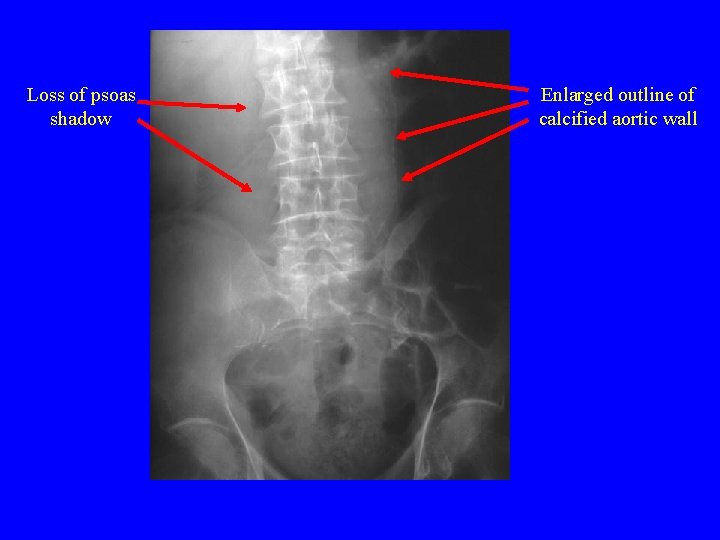

Diagnosis Imaging • Plain Films – Enlarged outline of calcified aortic wall • A retrospective review showed that 65% of x-rays form RAAA had calcified aortic wall – Loss of psoas shadow • Abdominal U/S – Sensitive in detecting aneurysm but not in detecting rupture • Abdominal CT – Most accurate method – See presence of retroperitoneal blood (77% sensitive and 100% specific)

Loss of psoas shadow Enlarged outline of calcified aortic wall